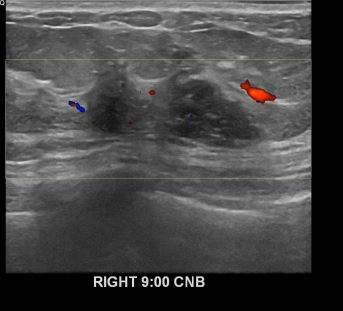

아산유외과개원후652번째유방암진단

상기환자 외부검사상 이상소견으로 내원하신 50대여성으로 우측유방의 의심스러혹

조직검사시행해 유방암 진단되었습니다.